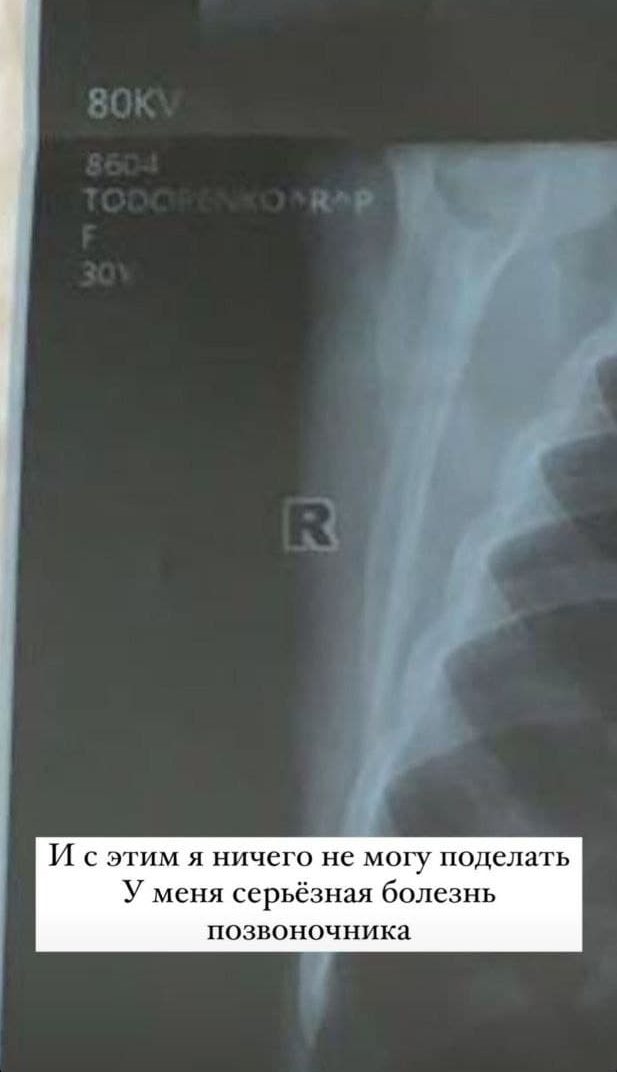

31-летняя звезда отправилась в очередную командировку, но неожиданно проснулась в отеле с болью в спине. В Stories Регина поделилась рентген-снимком, подписав (пунктуация и орфография сохранены – прим. ред.): «И с этим я ничего поделать не могу. У меня серьёзная болезнь позвоночника. Из-за болезни мне с детства нельзя было делать многие вещи, доступные другим детям. Если честно, я просто хотела быть такой же нормальной, как и все дети. Хотела, чтобы мне позволяли прыгать на батутах, прыгать на банджи, хотела кататься на коньках. Я всю жизнь так хотела быть нормальной, что доказывала себе, что смогу делать даже больше, чем нормальные дети!

Один из моих главных страхов быть несвободной. И неспособной сделать то, что хочешь. Глупый страх? Меня всегда вдохновляли истории людей, которые шли против системы. Про единственного человека без ног, покорившего Эверест Марка Инглиса, который лишился обеих ног, но не расстался со своей мечтой, много тренировался и покорил самую высокую вершину, с трудом поддающуюся даже обычным людям. После таких историй мне хочется жить. У этого всего есть плюсы. Доказывая себе, что боль меня не ограничивает, я: облетела целую планету; провела 230 000 километров в воздухе; прыгнула в Замбии с высоты 111 метров; погрузилась на глубину полукилометра; опустилась в недра Земли на 400 метров; прыгнула с парашютом с высоты 4000 метров. Разве я сделала бы это, если бы у меня не было стимула? Эта боль напоминает мне, что нужно проснуться как можно раньше и начинать проживать жизнь. Боль – это мое личное напоминание каждый день, что жизнь не бесконечна. Что рядом существует смерть».

При этом подробности своего диагноза Тодоренко не раскрыла. Желаем скорейшего выздоровления Регине!